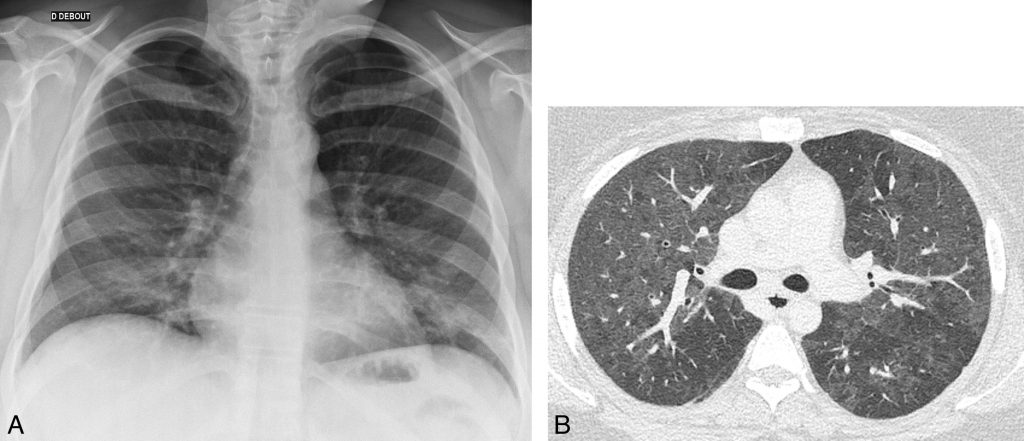

Chez les sujets greffés ou infectés par le VIH, la présence de « verre dépoli » bilatéral étendu suggère le diagnostic de pneumocystose (figure 96.4).

Fig. 96.4. Radiographie et scanner thoraciques.

A. Radiographie de thorax réalisée chez une patiente porteuse d’une infection par le VIH présentant une dyspnée fébrile. Pas d’anomalie parenchymateuse. B. Scanner thoracique réalisé chez la même patiente qu’en A. Plages de « verre dépoli » bilatérales diffuses, peu denses, traduisant une pneumocystose pulmonaire.

Source : CERF, CNEBMN, 2022.